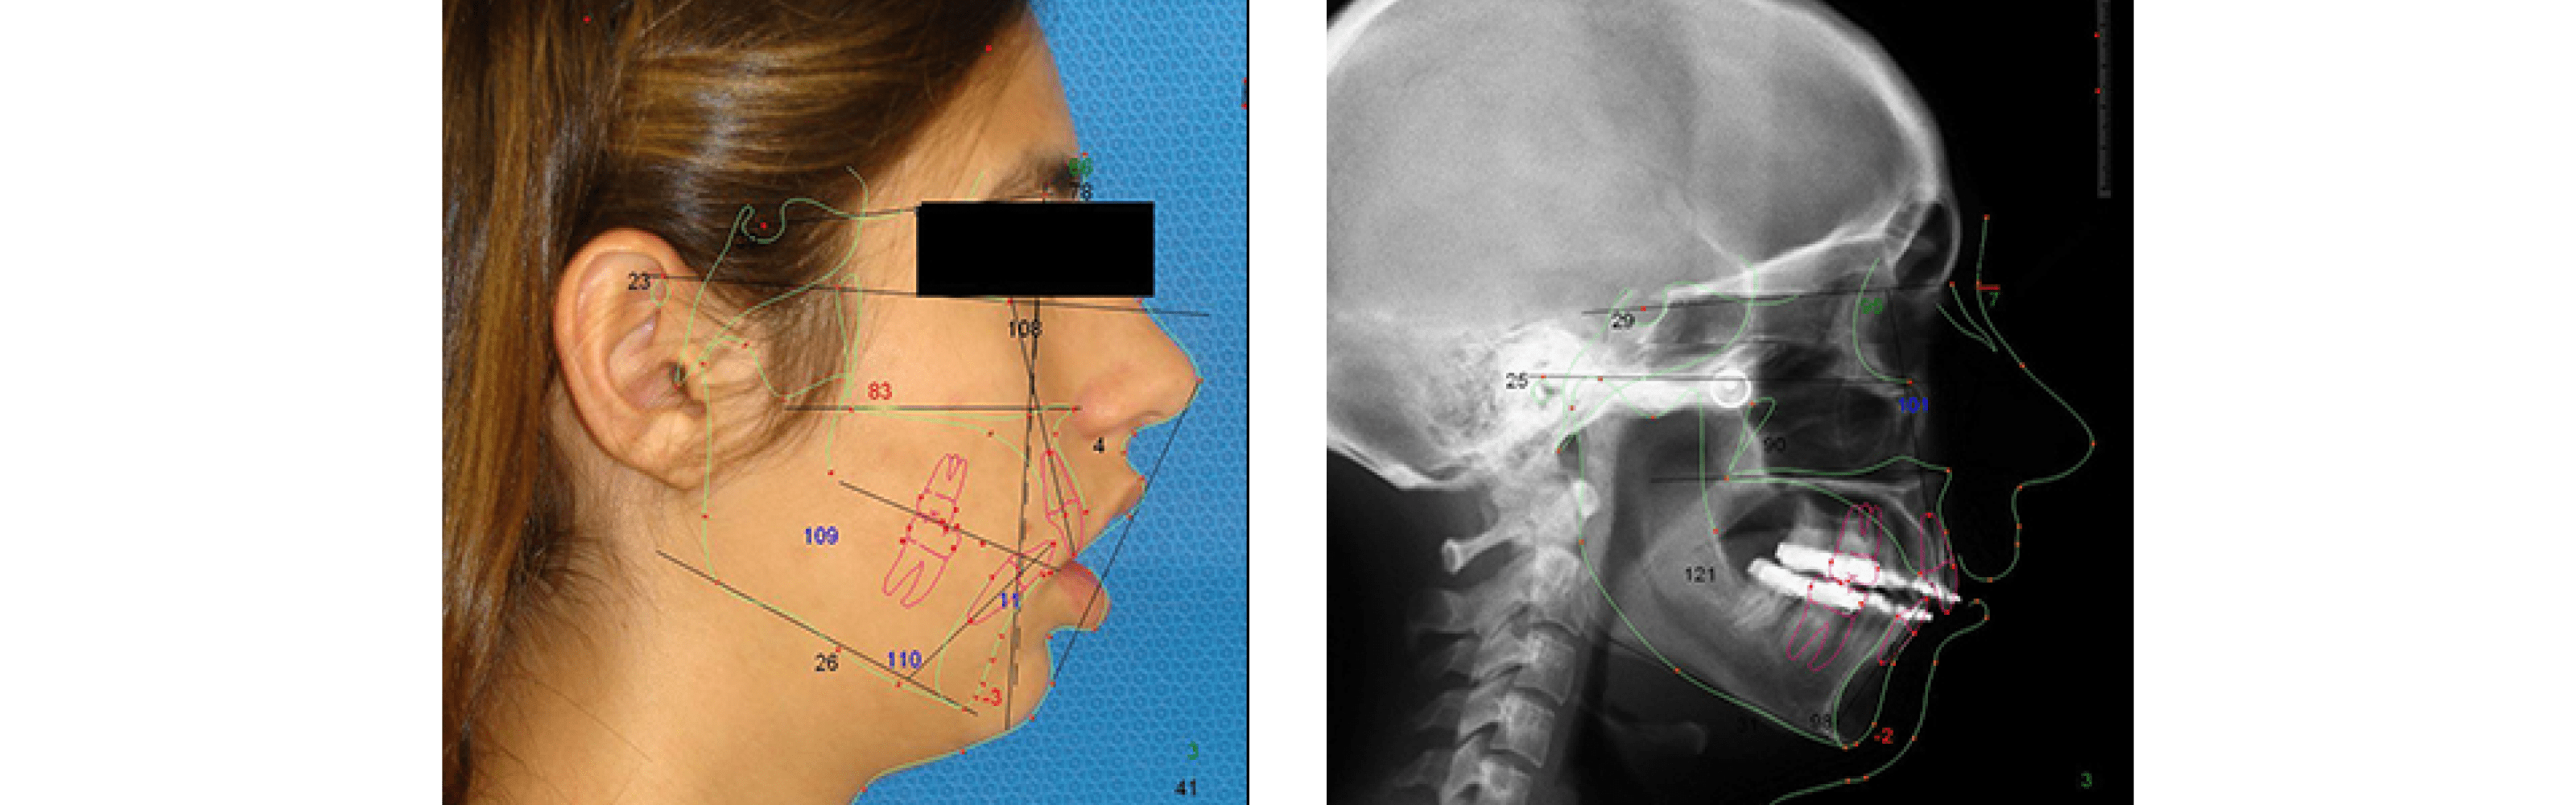

Corrective Jaw Surgery (Orthognatic)

Orthognathic surgery is needed when jaws do not meet correctly and/or teeth do not seem to fit with jaws. Teeth are straightened with orthodontics and corrective jaw surgery repositions misaligned jaws. This not only improves facial appearance, but also ensures that teeth meet correctly and function properly. The causes of a misaligned jaw go from birth defects, trauma or abnormal growth.

Corrective Jaw Surgery

Who needs orthognathic surgery?

The most common conditions associated with misaligned jaws are: mandibular prognathism (enlarged mandible), mandibular retrognathism/micrognathism (small mandible), open bite (separation between the upper and lower teeth) and vertical maxillary excess (excessive anterior teeth show and gummy smile). Orthodontics alone can correct bite problems when only the teeth are involved. Orthognathic surgery may be required for the jaws when repositioning is necessary.

What are the signs and symptoms of a misaligned jaw?

While a greatly protruding overbite or underbite is easily discernible, a misaligned jaw is much more subtle. Inadequate facial appearance is the main reason of patients seeking surgical treatment. You should also get an evaluation by an oral & maxillofacial surgeon if you suffer from any of the following symptoms: speech problems; chewing, swallowing, and/or biting that are painful or difficult, jaw pain (could be the result of temporomandibular joint disorder) and/or difficulty breathing (snoring).

What are treatment options?

The first step in repositioning a misaligned jaw is a thorough examination through x-rays, photos and models of your jaws and teeth. This type of procedure typically has to be coordinated together between your oral & maxillofacial surgeon and your orthodontist. The latest will then align your teeth with braces and the surgeon will operate in the maxilla, mandible or both jaws. The procedure is performed in the hospital under general anesthesia and the patient can be discharge the same day or the day after the surgery. Once surgery is completed, your teeth and jaws will have been moved into a new, more attractive position that will provide you with better jaw functionality and excellent facial appearance. The results of orthognathic surgery are permanent.

How is the recovery process?

The pain in recovering from corrective jaw surgery is comparable to having your wisdom teeth extracted. You should expect pain, swelling, and bruising; numbness around your jaw bone for several weeks to months; sometimes elastics fitted to your jaw to keep your new bite in place as your bones heal, consuming a blended, liquid diet for two weeks before moving into softer foods like pasta and eggs for the next four to six weeks, being absent from work for a week or two and engaging in zero physical activity for three to four weeks.